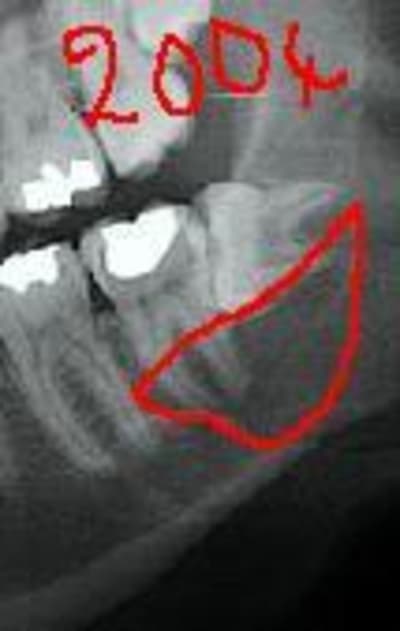

Extraction en 2004

La patiente ne revient pas après, pano demandé par un confrère en 2007 mais la patiente ne retourne pas le voir

j'ai le scan mais pas ici la corticale linguale est reduite à sa plus simple expression et le kyste remonte sur le trajet du nerf et s'etend aussi en vestibulaire

à priori 31/03/2006 pas si vieux que ça je croyais que c'etait 2004, donc évolution rapide